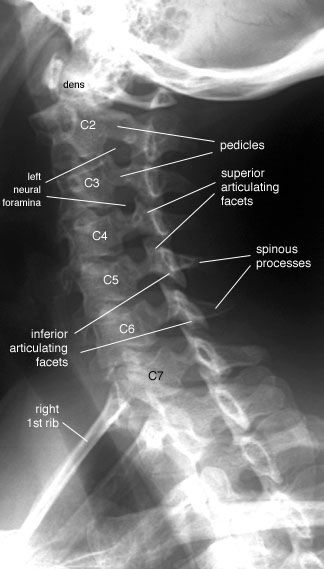

1.X-Ray:

It is easiest mean to image the spine.X-ray reveals alignment and degenerative changes of the bones.The spaces for the discs are seen as well, but no pictures are seen of the spinal cord,nerves or actual disc material. Unsuspected bony pathology, such as fractures,dislocations and cancer metastases, are quickly identified with X-ray.